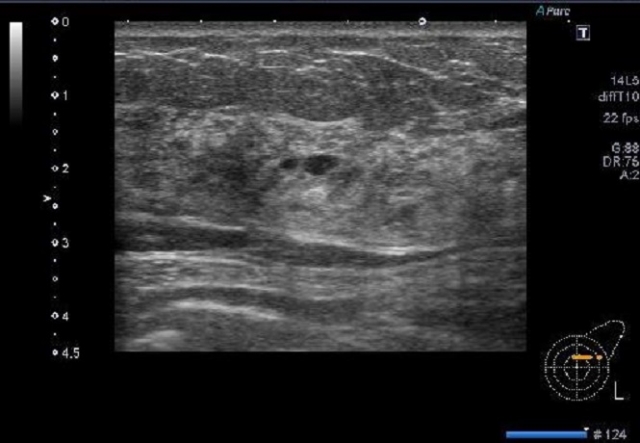

超音波画像診断装置(エコー)の特徴|安全でリアルタイムな観察が可能

超音波画像診断装置、いわゆるエコーは、体の内部をリアルタイムで観察できる評価機器です。放射線を使わないため安全性が高く、何度検査しても身体への負担が小さい点が大きな特徴と言えます。接骨院・鍼灸院でも、筋肉や腱、靭帯、関節周囲の状態を確認しながら施術方針を決めたいときに、とても役立つツールになっています。

組織の状態をリアルタイムで可視化できる理由

エコーは、超音波を体内に送り込み、その反射を拾い上げて画像に変換しています。異なる組織はそれぞれ反射の仕方が違うため、その差を利用して陰影や形として画面に映し出すことができます。筋肉がどの方向に走っているのか、腱がきちんと滑っているのか、靭帯に腫れや断裂がないかなどを、その場で確認できるのが大きな強みです。静止した状態だけでなく、実際に動かしながら観察できるため、「どの動きで痛みが出るのか」を具体的な画像として捉えられます。

画像診断で使用する周波数の特徴

エコーで使われる超音波は、治療用と比べて周波数が高いという特徴があります。高い周波数を使うことで、細かな組織の境目や小さな変化も映し出しやすくなりますが、その分だけ深くまでは届きにくくなります。そのため、目的とする部位に合わせてプローブや設定が選ばれています。浅い場所を詳しく見たい場合にはより高い周波数を、やや深い場所を確認したい場合には少し低めの周波数を使うといった具合です。この調整により、診たい部位をできるだけ鮮明に映す工夫がされています。